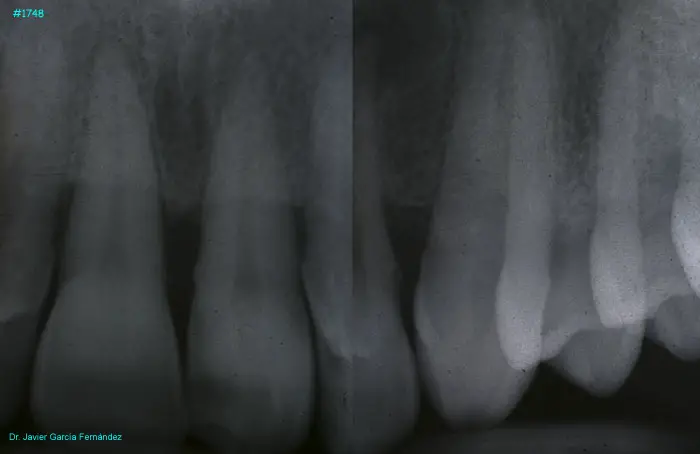

image 16